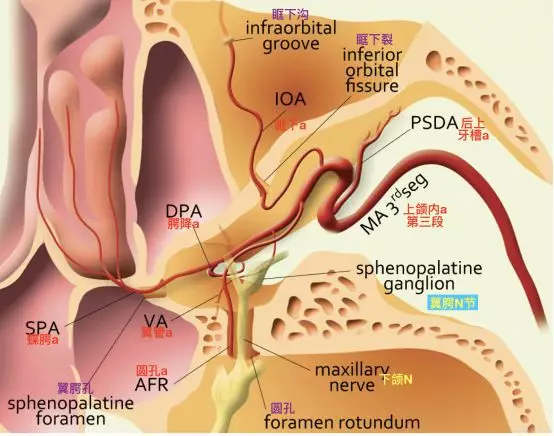

圆孔动脉由上颌内动脉翼腭段发出,通过圆孔,主要供应圆孔内的上颌神经。一般情况下,圆孔动脉很细小。

右侧翼腭窝解剖模式图,上面观(Tanoue 2013)。可见圆孔动脉从翼腭窝经圆孔入颅。

翼管神经和翼管动脉向前走行于蝶窦底下方(Osawa 2009)。可见走行至圆孔,和V2伴行的圆孔动脉。也可见颈内动脉海绵窦段与圆孔的关系也很密切。

要注意在正常情况下,从颈内动脉海绵窦段发出的下外侧干,可能有分支至圆孔处,与上颌内动脉发出的圆孔动脉有吻合。

在颈内动脉起始段狭窄或者闭塞时,上颌内动脉翼腭段可能通过两个分支,对颈内动脉代偿供血。其一通过翼管动脉,经翼管至破裂孔,与颈内动脉岩段发出的翼管动脉吻合代偿供血。其二就是通过圆孔动脉,经圆孔入颅,在圆孔附近与颈内动脉海绵窦段发出的下外侧干形成代偿供血。